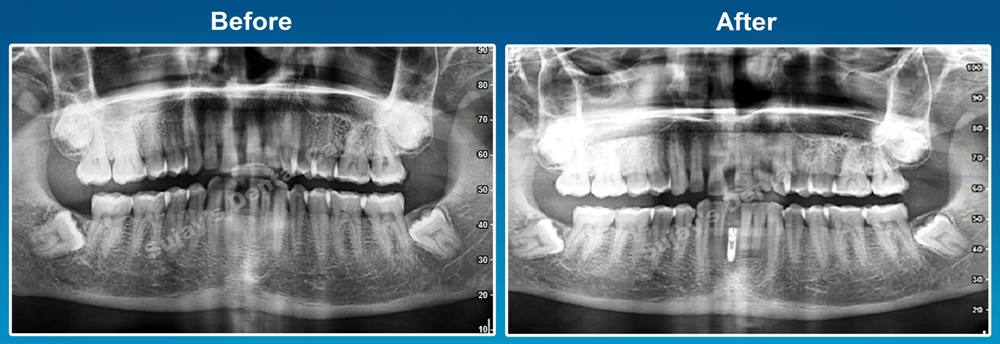

As a part of Evidence based treatment we took full mouth OPG.

After examining OPG x-ray of the teeth, our team of dentists decided to go with restoration of the lower missing tooth using dental implant.

Root canal treatment was done wrt 21. Upper midline diastema closure was done using crowns.